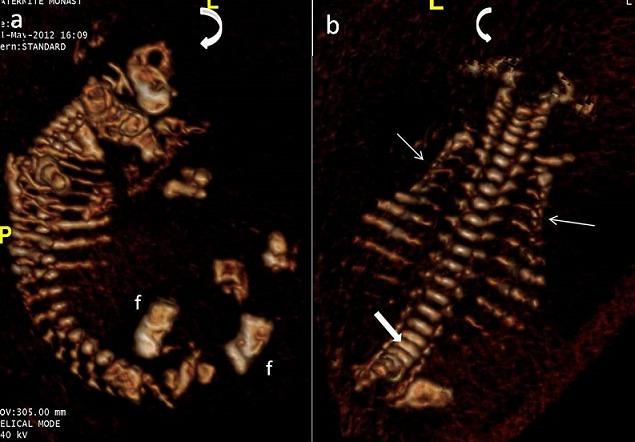

Osteogenesis imperfecta (OI) is a heterogeneous group of diseases affecting type I collagen and characterized by bone fragility. Lethal forms are rare and are characterized by micromelia associated with limb deformities. We report two cases of prenatally diagnosed lethal OI. Patients underwent ultrasound examination at 17 and 25 weeks of amenorrhoea, supplemented with fetal skeletal CT scanning in one case. Therapeutic abortion was recommended in both cases.

成骨不全症(OI)是一组影响I型胶原蛋白且以骨脆性为特征的异质性疾病。致死型较为罕见,其特征为伴有肢体畸形的短肢畸形。我们报告两例产前诊断为致死型OI的病例。两名患者分别在停经17周和25周时接受了超声检查,其中一例还进行了胎儿骨骼CT扫描。两例均建议进行治疗性流产。